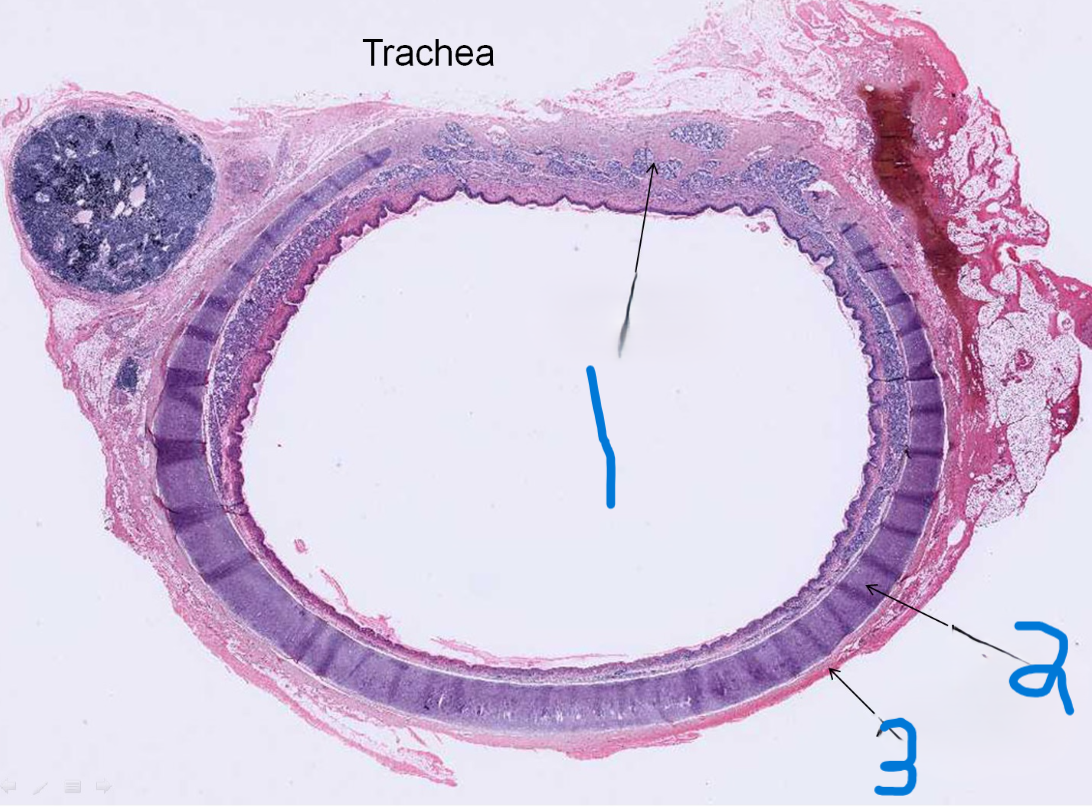

What is depicted by #1

Hyaline cartilage

What is depicted by #2

Adventitia

What is depicted by #3